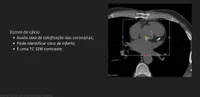

Qual o exame da imagem? O que ele avalia bem?

Escore de cálcio. Taxa de calcificação.

Angiografia de tórax. Grau de estenose

Ressonância magnética. Músculo cardíaco.

Angiotomografia com contraste. Avalia tromboembolismo.